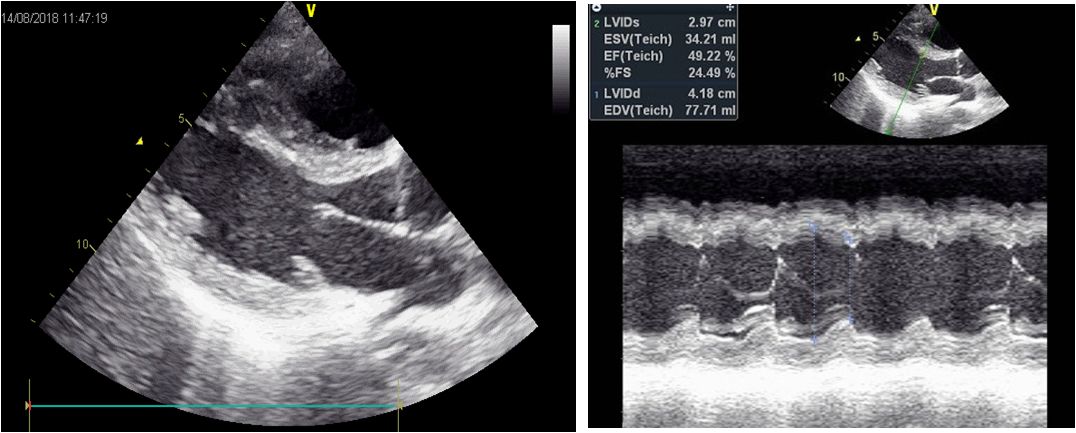

心脏彩超(入院第3天)

(左西孟旦后24h)左心室舒张末内径42mm,EF:49%